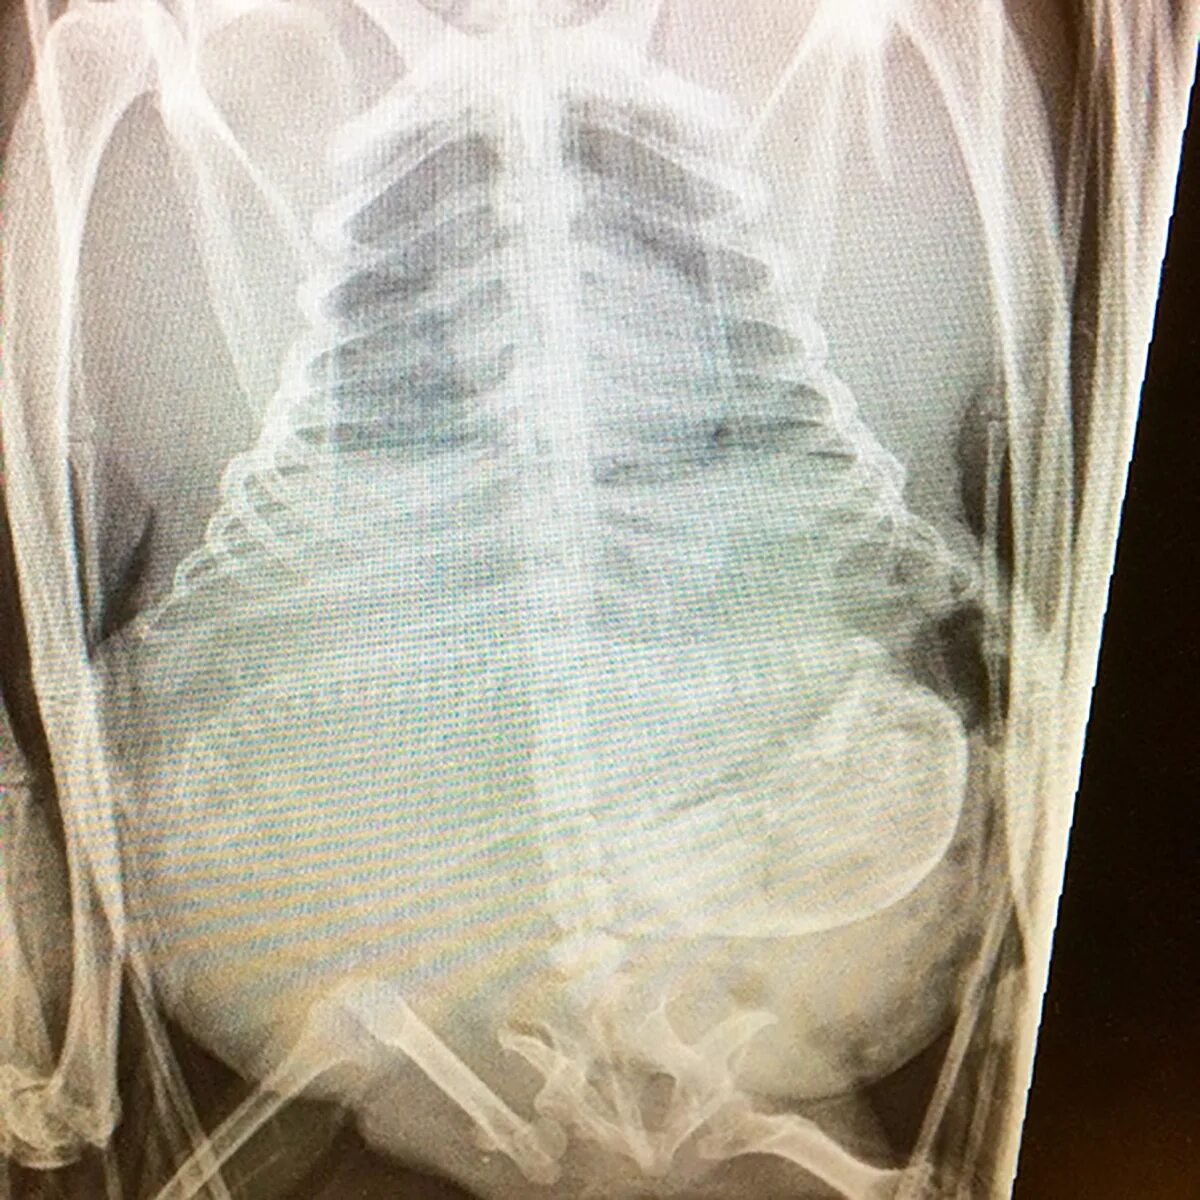

Делала рентген при беременности